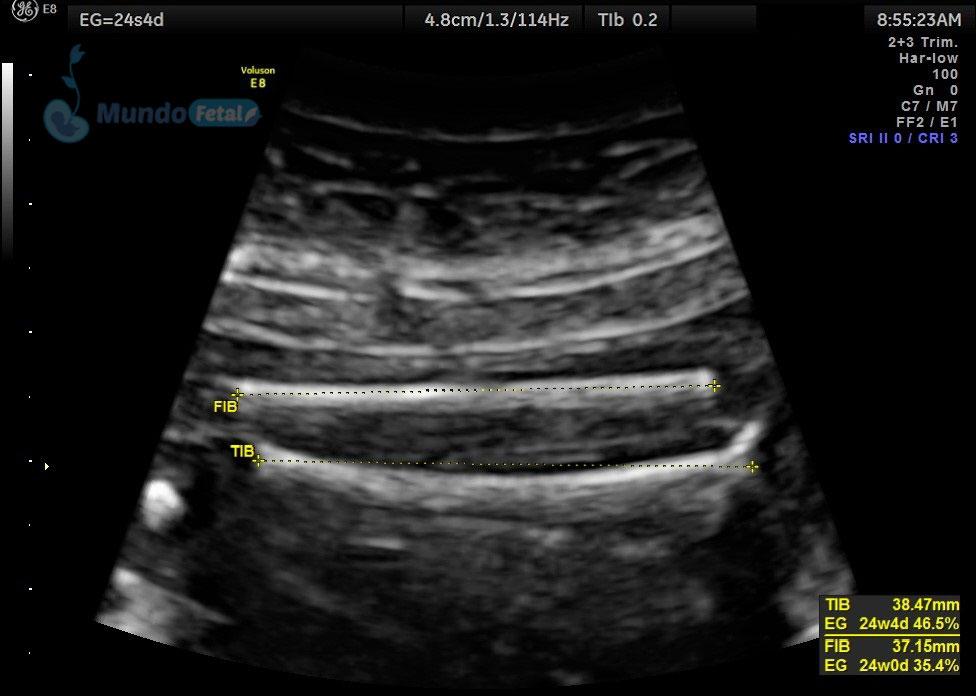

LONGITUD-CERVICAL1